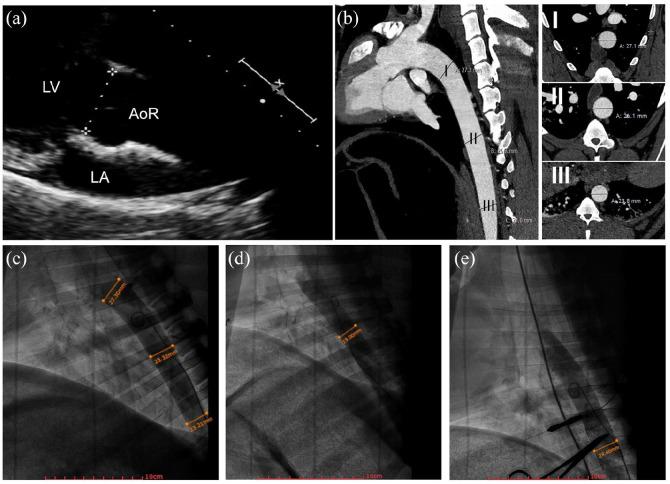

The save deployment of intra-aortic percutaneous mechanical circulatory support devices is highly dependent on the inner aortic diameter. Finding the anatomically and ethically most suitable animal model for performance testing of new pMCS devices remains challenging. For this study, an ovine model using adult ewes of a large framed breed (Swiss White Alpine Sheep) was developed to test safety, reliability, and biocompatibility of catheter-mounted mechanical support devices placed in the descending thoracic aorta. Following the drawback of fluctuating aortic diameter and device malfunction in the first four animals, the model was improved by stenting the following animals with an aortic stent. Stenting the animals with an intra-aortic over the balloon stent was found to standardize the experimental set-up and to avoid early termination of the experiment due to non-device related issues.

经导管主动脉内机械循环支持装置的安全部署高度依赖于主动脉内直径。为了对新型经皮机械循环支持装置进行性能测试,寻找在解剖学和伦理学上最合适的动物模型仍然具有挑战性。在这项研究中,我们建立了一个绵羊模型,使用成年的大型框架品种(瑞士白阿尔卑斯绵羊)的母羊来测试放置在降主动脉中的导管式机械支撑装置的安全性、可靠性和生物相容性。在前四只动物中,由于主动脉直径波动和装置故障,该模型存在一些缺陷。随后,我们对后续的动物进行了主动脉支架置入术,改进了该模型。我们发现,使用球囊内主动脉支架对动物进行支架置入可以使实验设置标准化,并避免因非装置相关问题而导致实验提前终止。